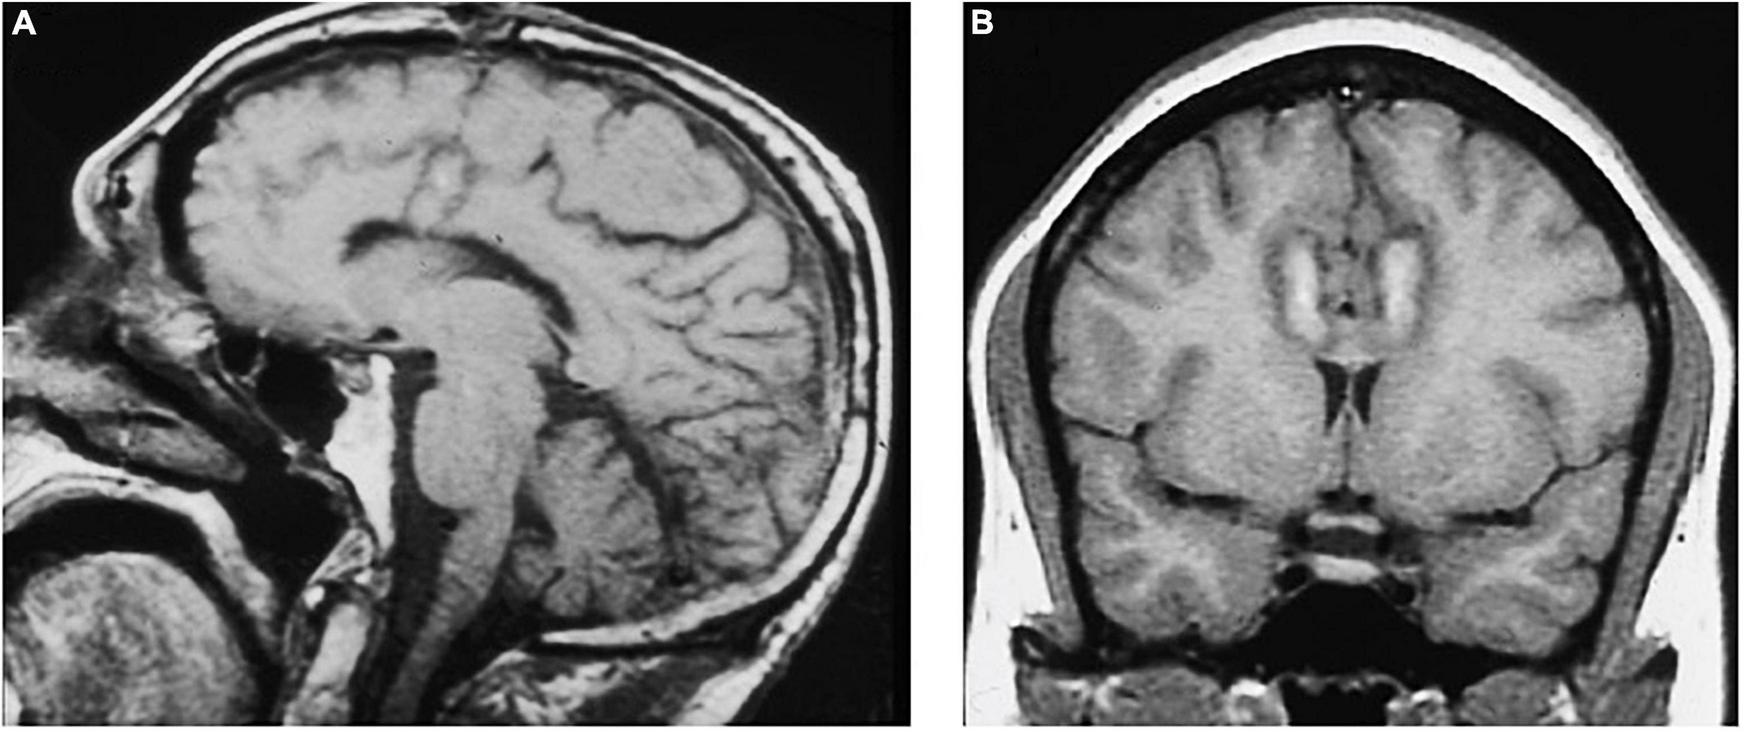

FIGURE 4

MRI-guided cingulotomy. (A) Sagittal and (B) Coronal T1-weighted MRI of acute single lesion cingulotomy.